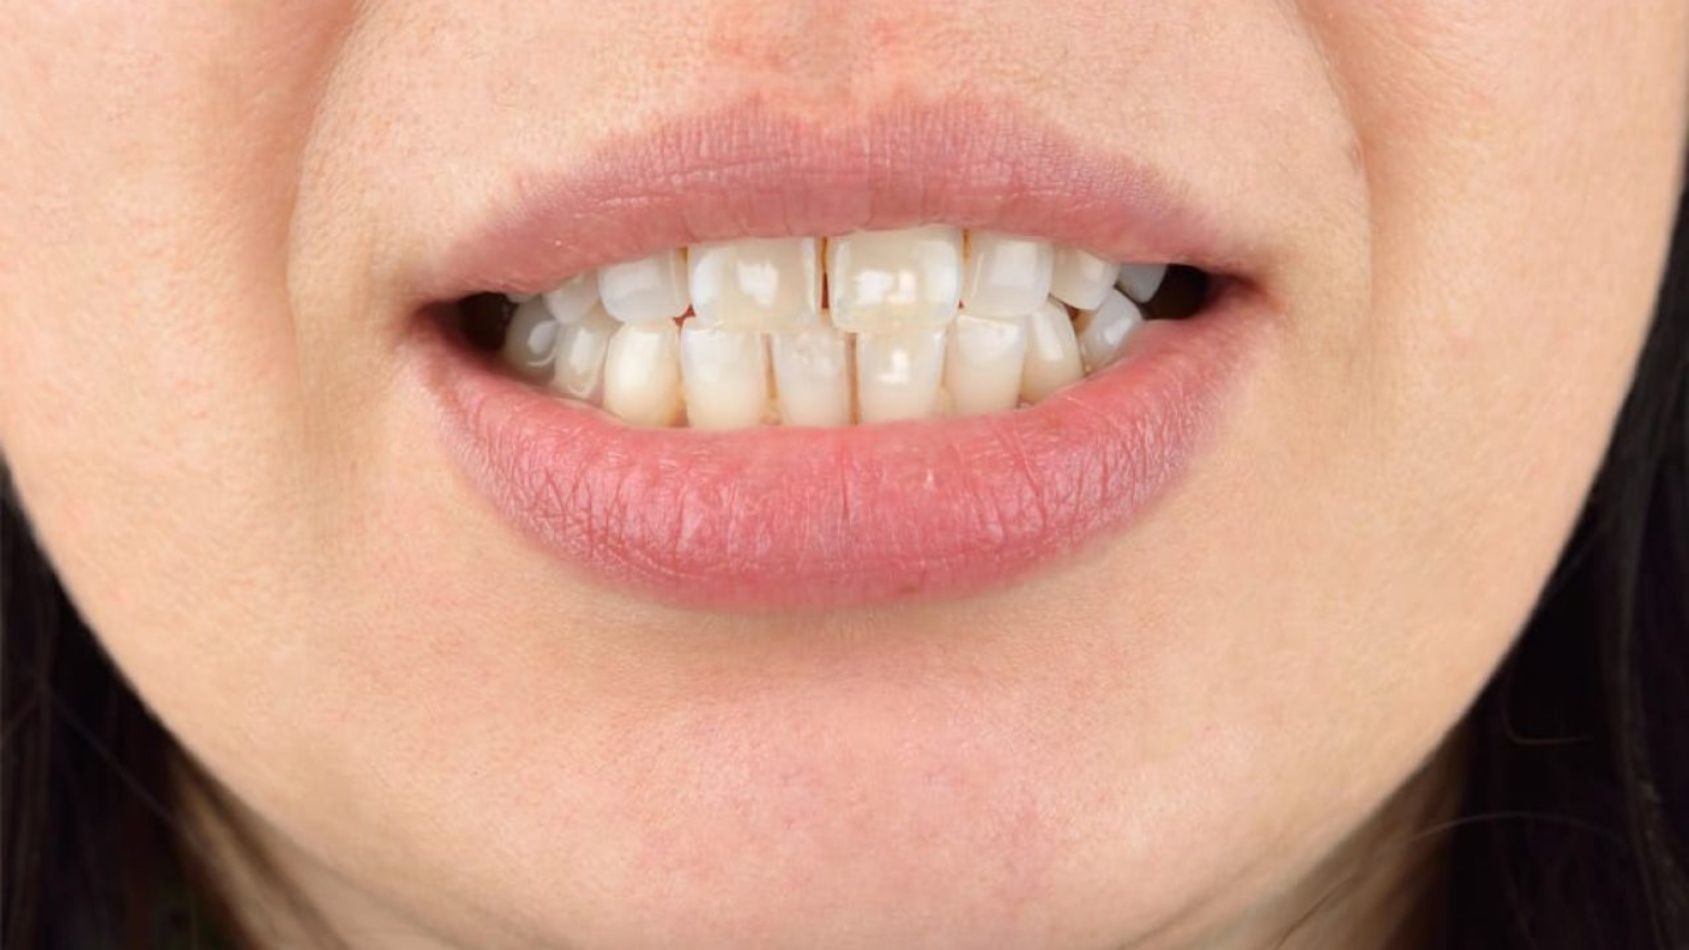

Lip Hemangiomas. This common lip discoloration is often caused by minor trauma such as that occurring at a dentist office, or even just biting your lip.

But there are various potential causes of a purple spot on your lip. Some of them are benign (not threatening to your health), while others could be signs of something more serious. The following list of conditions could help you narrow down what's behind the discoloration you're experiencing, but be careful not to self-diagnose – a healthcare professional is best-suited to diagnose and treat your condition. Some of the most common causes of a purple spot on the lip include: